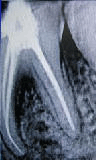

After RCT Filling |